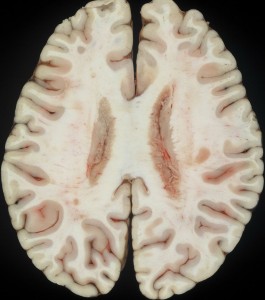

脳室上衣下浸潤(剖検例)

subependymal infiltration (autopsy)

1992年の剖検所見

大脳表面,脳幹部,脊髄くも膜下腔には腫瘍が見当たりませんが,側脳室を充満するように腫瘍が増殖しています。

側脳室壁に結節状の腫瘍が無数に認められます。これは今日では,内視鏡による脳室内観察で見ることができるものです。

上方が側脳室側です。脳との境にある脳室上衣 ependyumの下に腫瘍細胞が這うように浸潤しています。そこから血管周囲 Virchow-Robin spaceを通って脳深部に浸潤しています。

大脳深部(左)と小脳深部(右)には髄質血管に沿って浸潤します。これは髄芽腫などと同様の脳浸潤所見です。